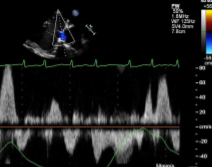

Given this HV PW trace, what would you expect to find when imaging the heart?

Elevated A-wave reversal

Expect to see:

↑RAP

RA enlargement

TR

RV dysfunction

RVVO or RVPO